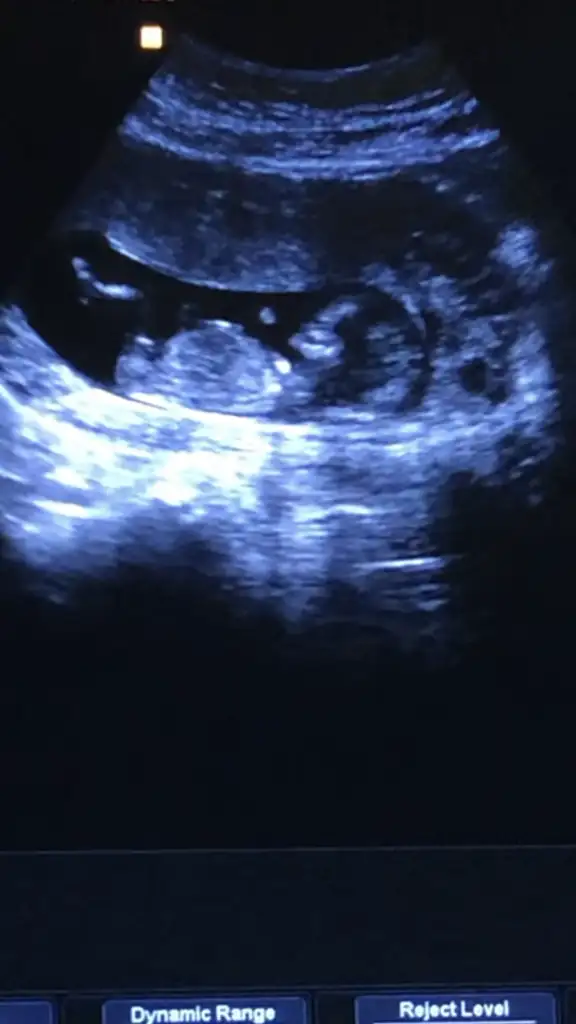

Ikra meyra canim bakar mısın Bi cinsiyet tahmini 15 haftalık

Kız gibielimdeki tüm usg görüntüleri bunlaryeterli olur mu ki tahmin için

ErkekKızlar biz de 12+2’deyiz. Bugün doktor randevumuz vardı ama cinsiyetini söylemek için erken dedi. Tahminlerinizi alabilir miyim?

Kız gibi ama emin olamadım cnm net degil usg başka varmı usg tekrar paylaşırmısın

13 hafta canımKaç haftalık usg sanki erkek gibi başka usgde paylaşın 12 13 haftalar

Erkek gibi